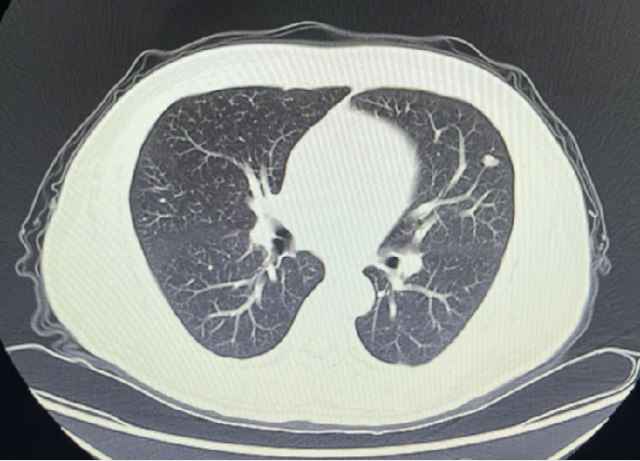

2023-05-03:

2023-08-01:

2023-11-08:

2024-02-28:

2024-05-17: